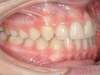

Cas 4 : Description

Chevauchement sévère. Traitement multibague sans extraction.

Avant

Après